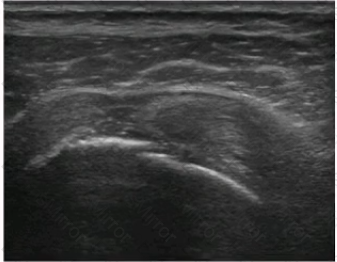

The orthogonal images of a supraspinatus tendon shown here are MOST consistent with which of the following?